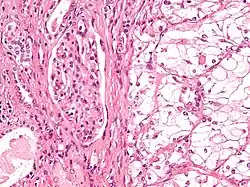

| Micrograph showing the most common type of kidney cancer (clear cell renal cell carcinoma). H&E stain. | |

The most common type of kidney malignancy is renal cell carcinoma,[35] which is thought to originate from cells in the proximal convoluted tubule of the nephron.[15][36] Another type of kidney cancer although less common, is transitional cell cancer (TCC) or urothelial carcinoma of the renal pelvis.[37] The renal pelvis is the part of the kidney that collects urine and drains it into a tube called the ureter.[37] The cells that line the renal pelvis are called transitional cells, and are also sometimes called urothelial cells. The transitional/urothelial cells in the renal pelvis are the same type of cells that line the ureter and bladder. For this reason TCC of the renal pelvis is distinct from RCC and is thought to behave more like bladder cancer.[37] Other rare types of kidney cancers that can arise from the urothelial cells of the renal pelvis are squamous cell carcinoma and adenocarcinoma.[15]

Renal cell carcinoma has been further divided into sub-types based on histological features and genetic abnormalities. The 2004 WHO Classification of the Renal Tumors of the Adults describes these categories:[41]

- Clear cell RCC